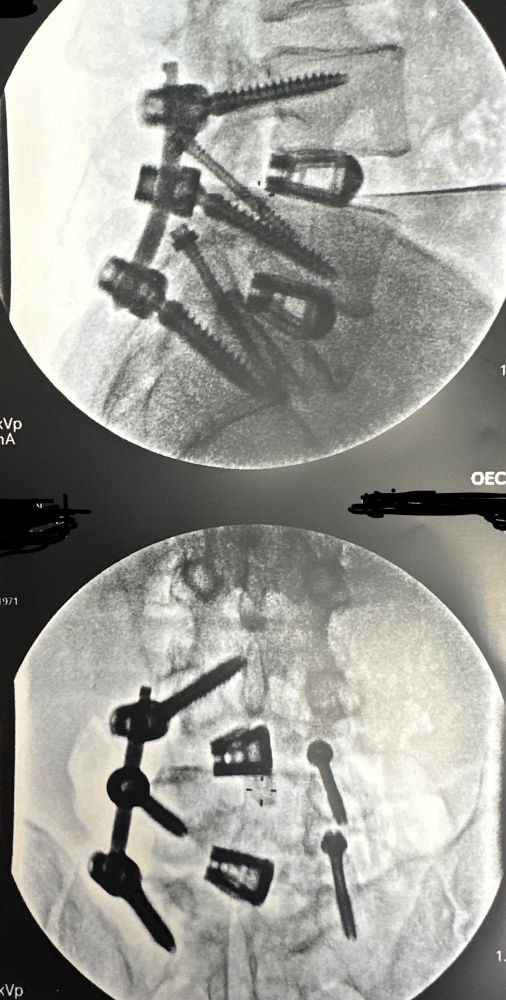

My first post!!! Minimally invasive spinal ambulatoryfusion. Two 2-inch incisions. Home in 2 hours! Avoid the big cut!!!!